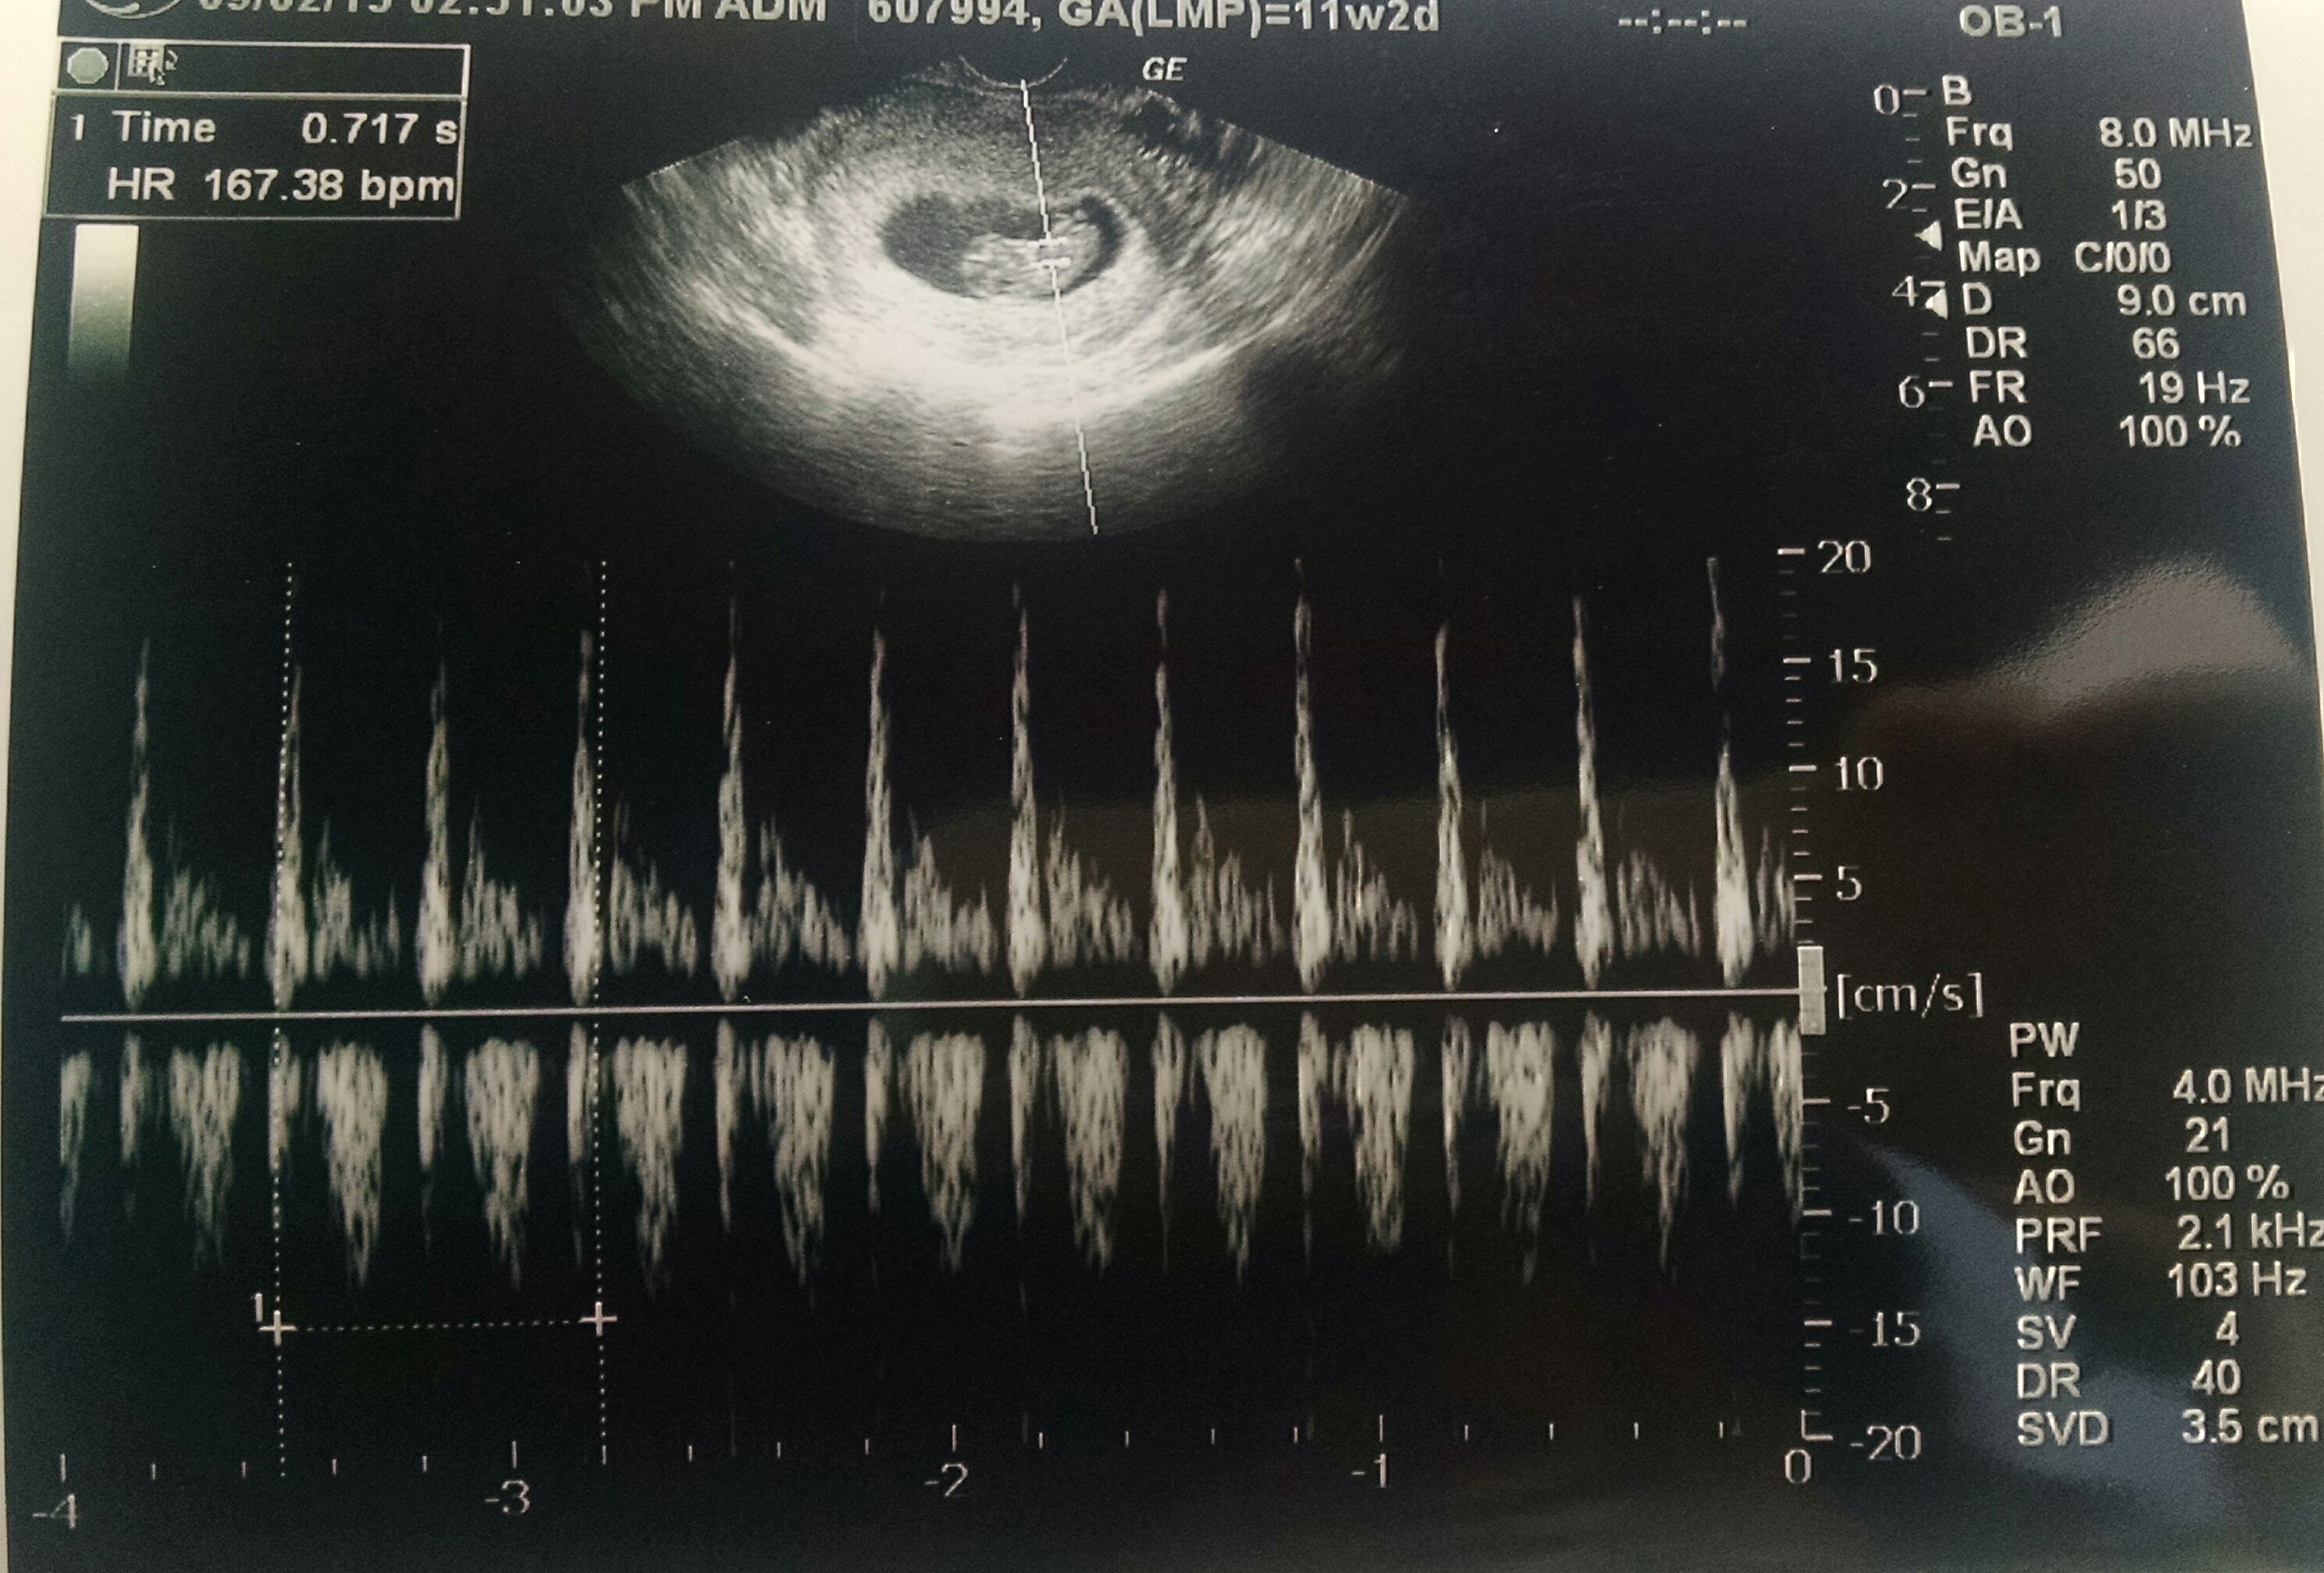

Had my second ultrasound today. Measuring 9w+2d. Baby was moving around so much! Looked like it was doing the robot It was my husband's first time seeing and hearing the heartbeat (167). Feeling so relieved since my morning sickness had really gotten better and I was getting worried..